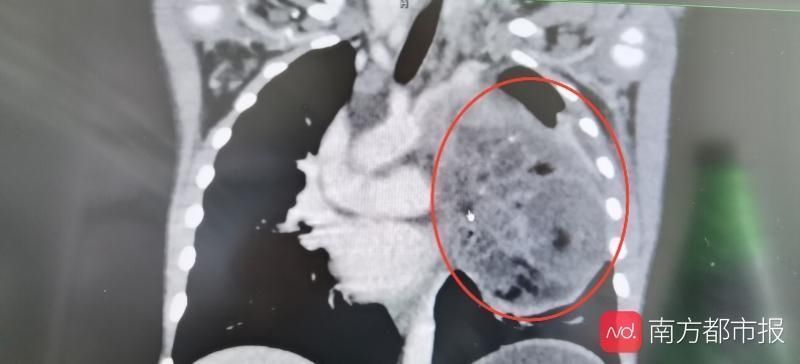

11月8日,3岁8个月的小星星因“发热伴咳嗽2周”入住中山大学附属第一医院。她在2周前无明显诱因出现发热,最高达39℃,伴咳嗽,呈刺激性干咳。检查发现原来致病的元凶是胸腔内长了一个11cm的巨大肿瘤,肿瘤完全占据了整个左侧胸腔,心脏、大血管和左肺完全被挤压到了对侧。

手术前,小星星的左侧胸腔已经被完全挤占